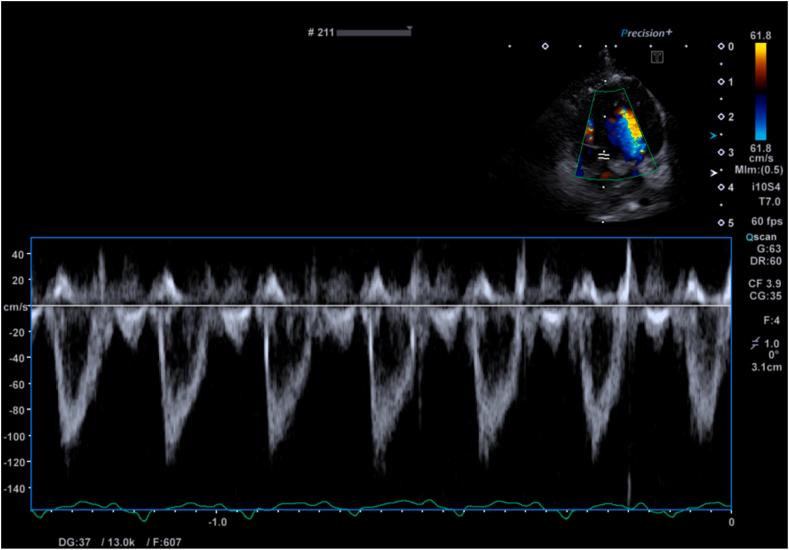

Bicuspid Aortic Valve in a Healthy Cat: Two- and Three-Dimensional Assessment.

• BAVs can be encountered in cats without clinical signs. • A BAV appeared to be an isolated cardiac abnormality in this cat. • 3D TTE can be successfully used in cats to characterize the aortic valve.

摘要

• 猫可能出现二叶式主动脉瓣(BAV)但无临床症状。

• 这只猫的二叶式主动脉瓣似乎是一种孤立的心脏异常。

• 三维经胸超声心动图(3D TTE)可成功用于猫以对主动脉瓣进行特征描述。